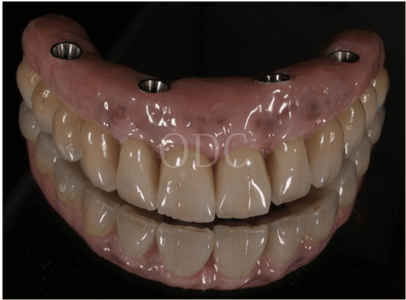

⑤ 美しい最終補綴

専属の歯科技工士により、芸術まで高められた最終補綴物を貴方に、心を込めて贈ります。これらのテクニックはほんの一部です。オールオン4は高度なインプラント技術を必要とする治療の1つです。後悔しない為にクリニック選びは慎重に行って下さい。

最終補綴1

最終補綴2

最終補綴3

最終補綴4

最終補綴5

最終補綴6